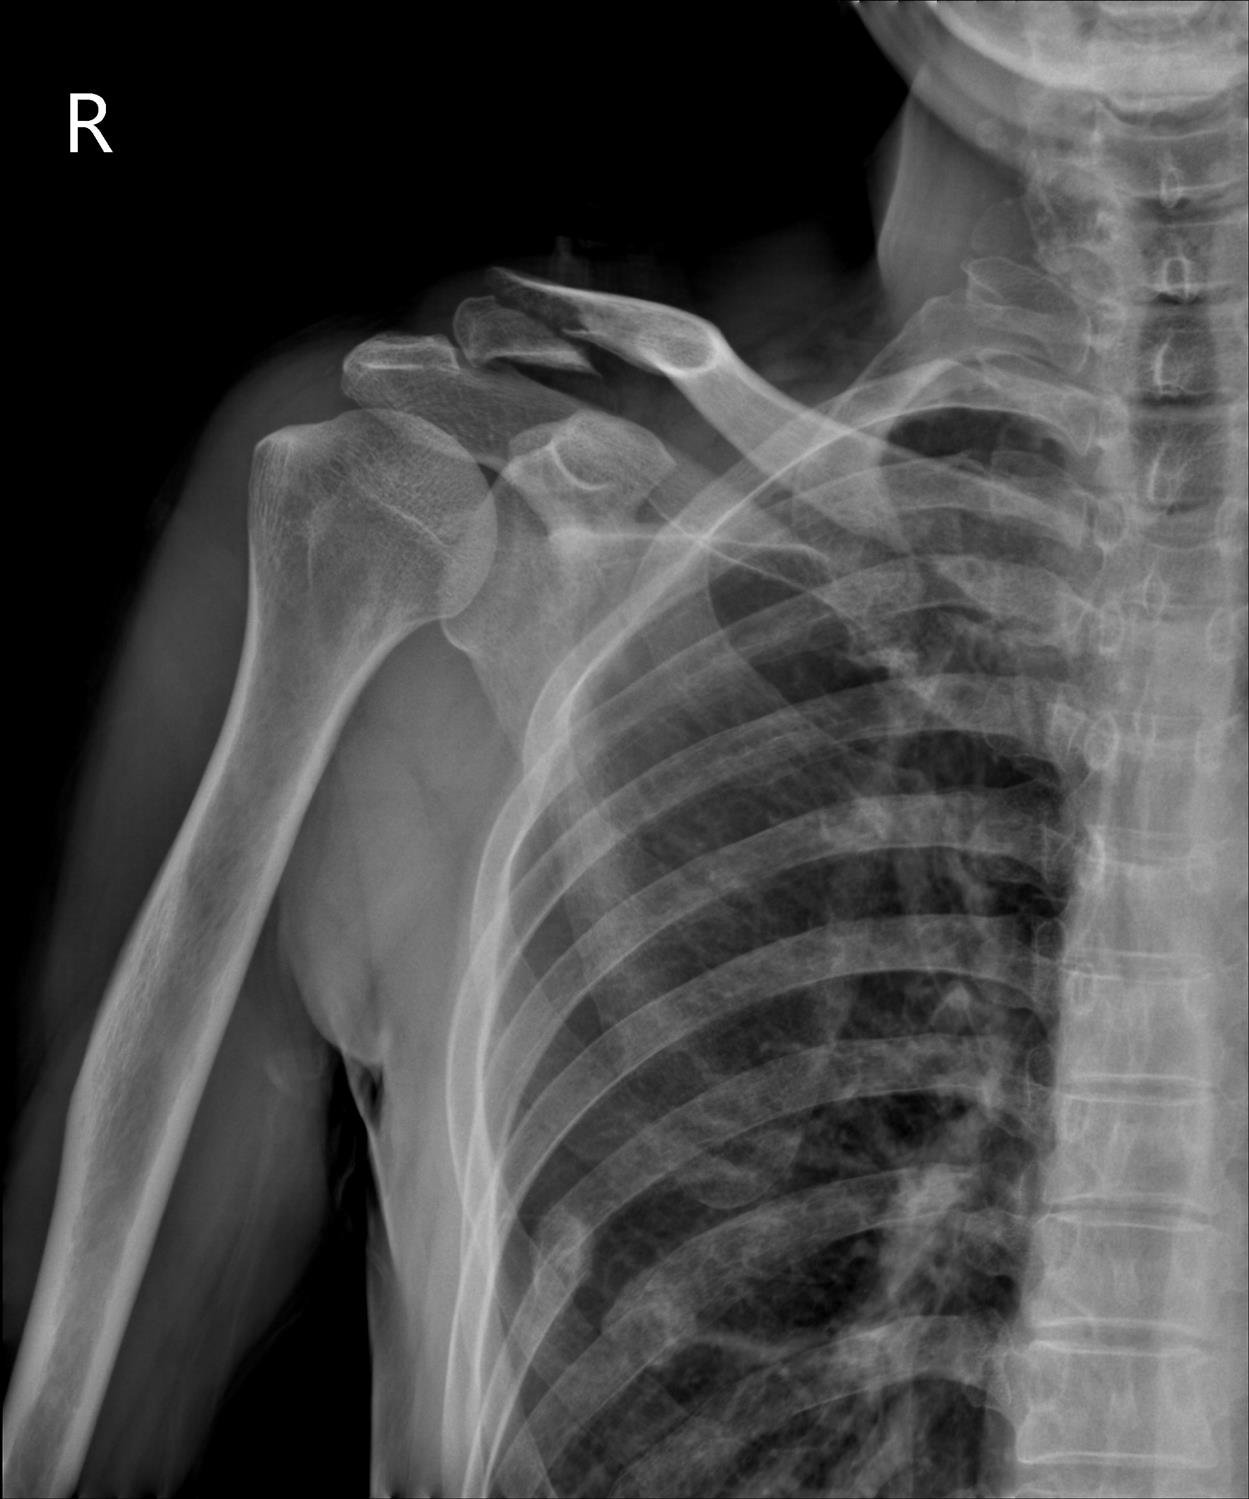

Imaging of a patient with a distal clavicle fracture with proximal

Plain AP Xray of a displaced right distal clavicle fracture (Neer type Where Is A Distal Clavicle Fracture Here we will look at the common causes and symptoms of clavicle fractures, how they are diagnosed and. Clavicle fractures usually occur at the. Clavicle fractures are the most common cause of collar bone pain and clavicle lumps. Clavicle fractures are classified into three types based on the location of the fracture: A description of these injuries typically departs from. Where Is A Distal Clavicle Fracture.